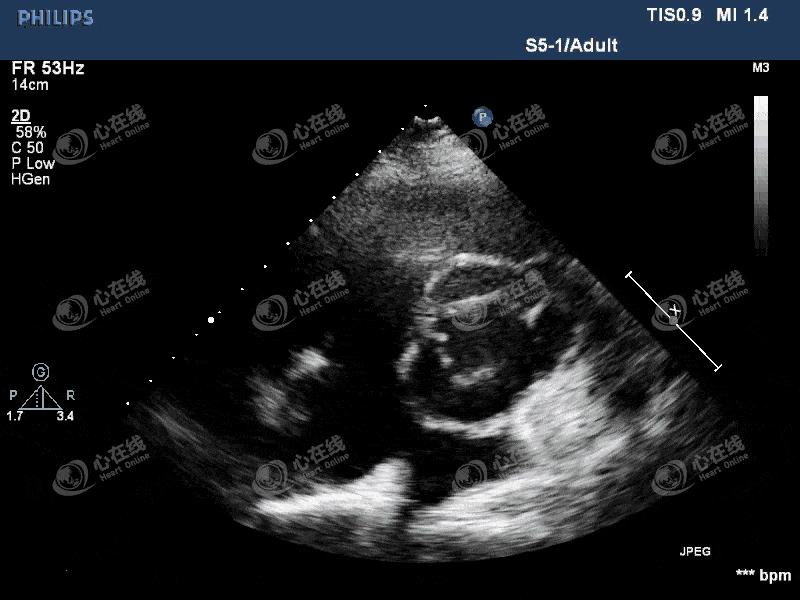

图1 左室长轴切面:左心饱满,主动脉瓣为人工机械瓣,缝合环活动度增大,主动脉根部前壁及后壁紧邻机械瓣处可见一隔膜样回声,其上可见破口,该处可见无回声区。